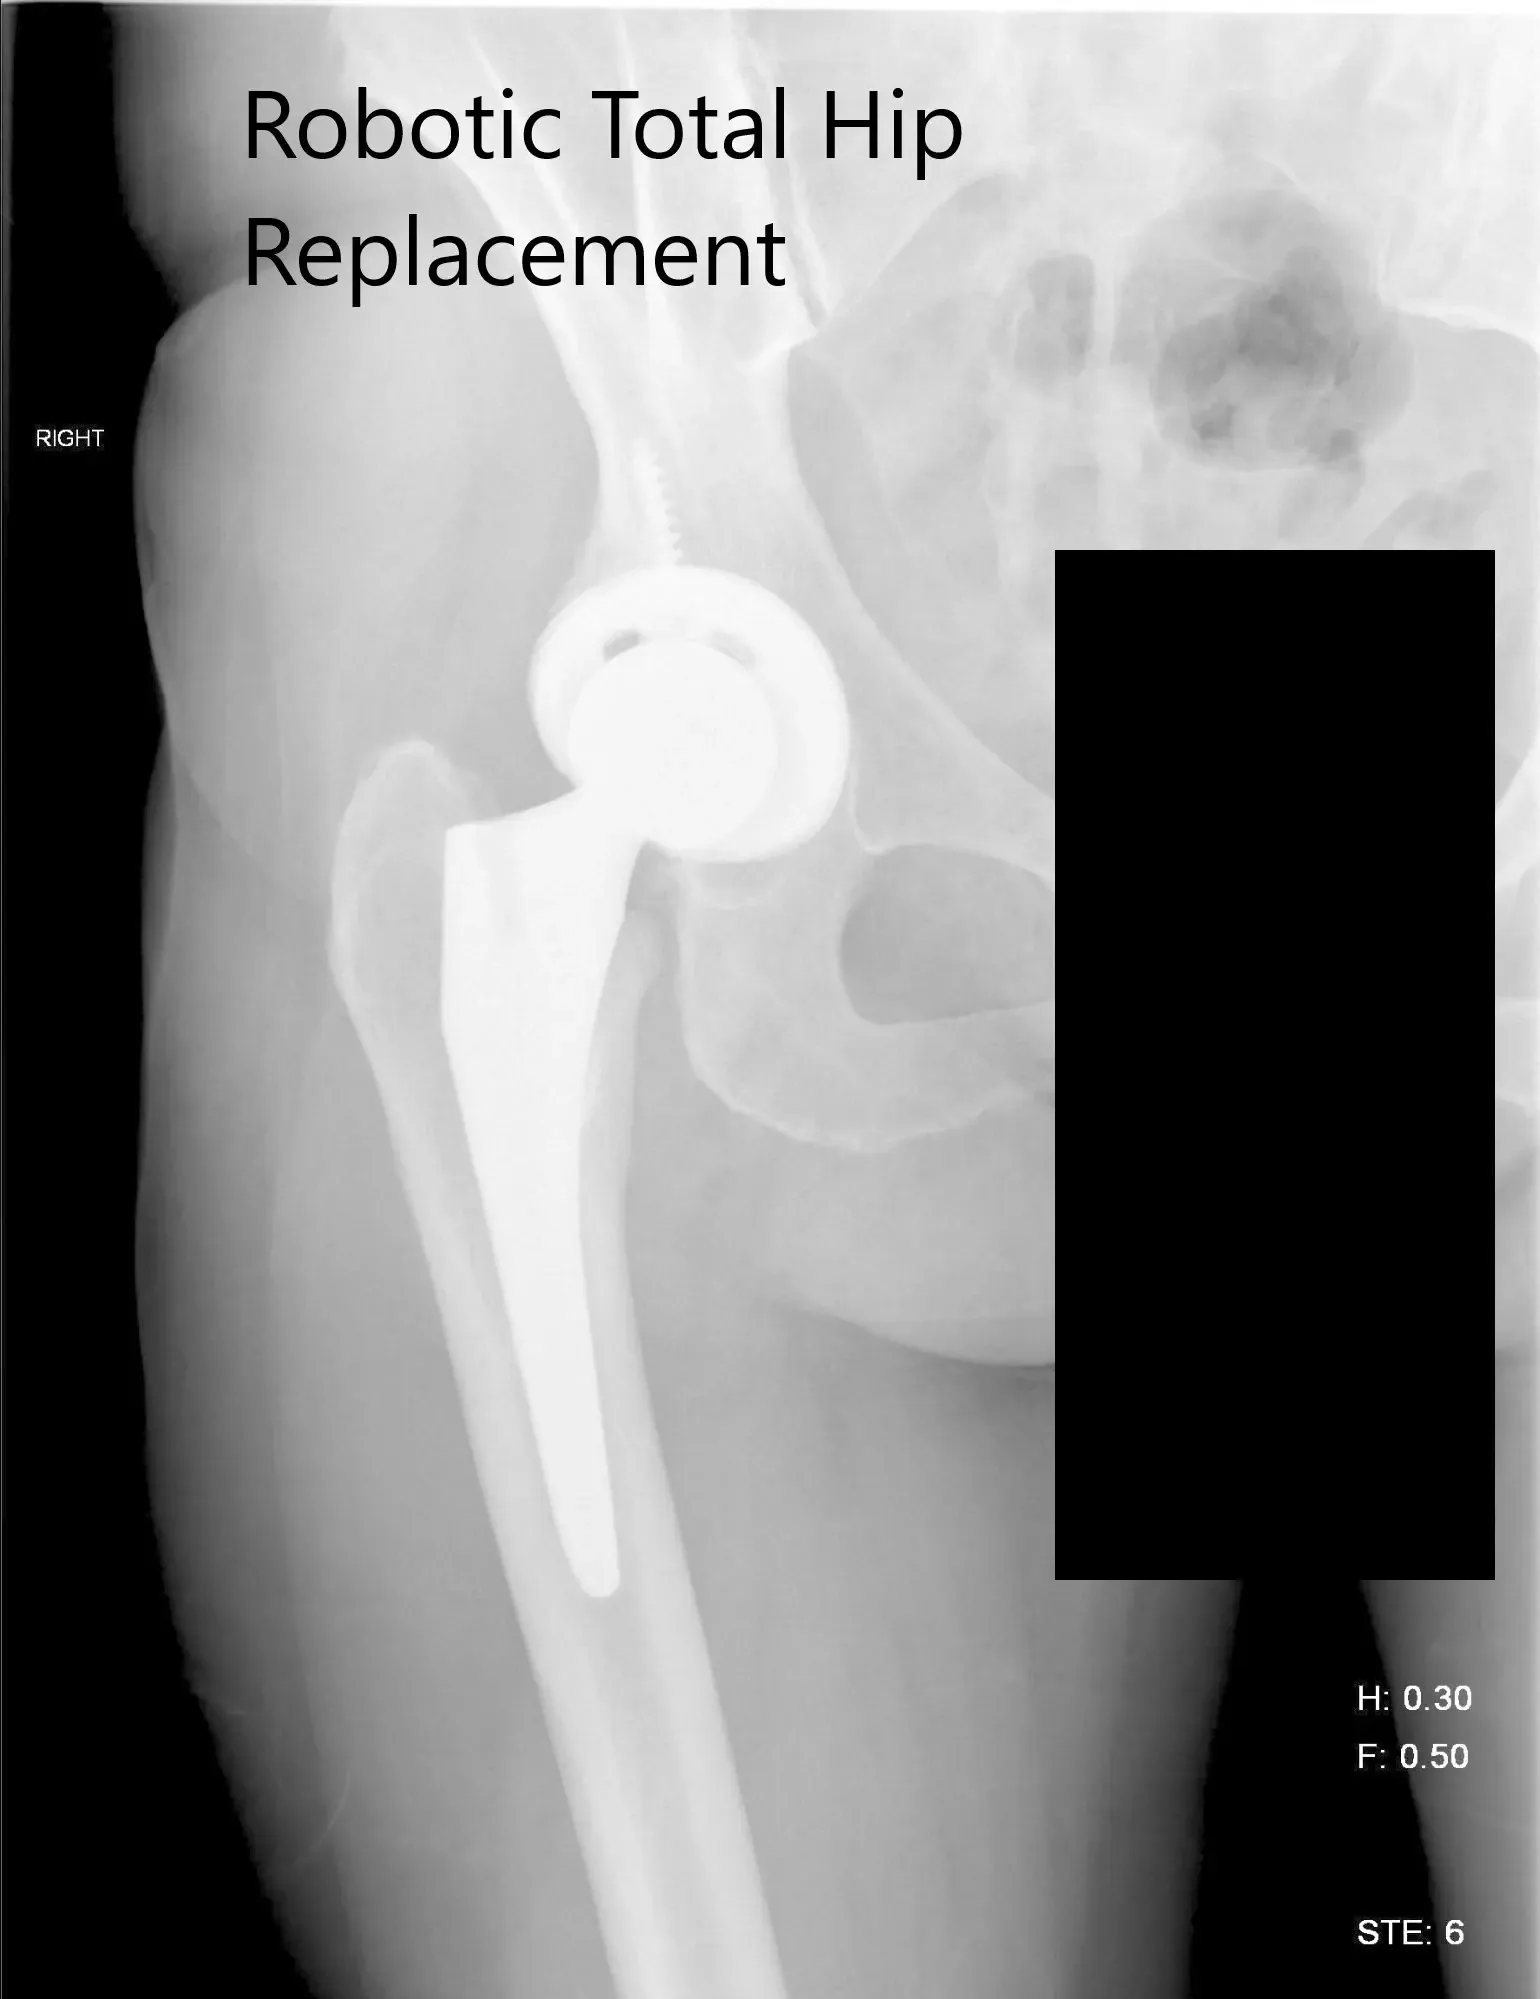

OPERATION: Robotic right total hip replacement.

IMPLANTS USED: Tritanium cluster shell 52-mm with 6.5-mm x 30-mm screw with a Trident shell. Zero degrees poly with a 127-degree stem with a ceramic head, outer diameter 32-mm minus 4.

Postoperative X-ray of the right hip showing AP and lateral view.